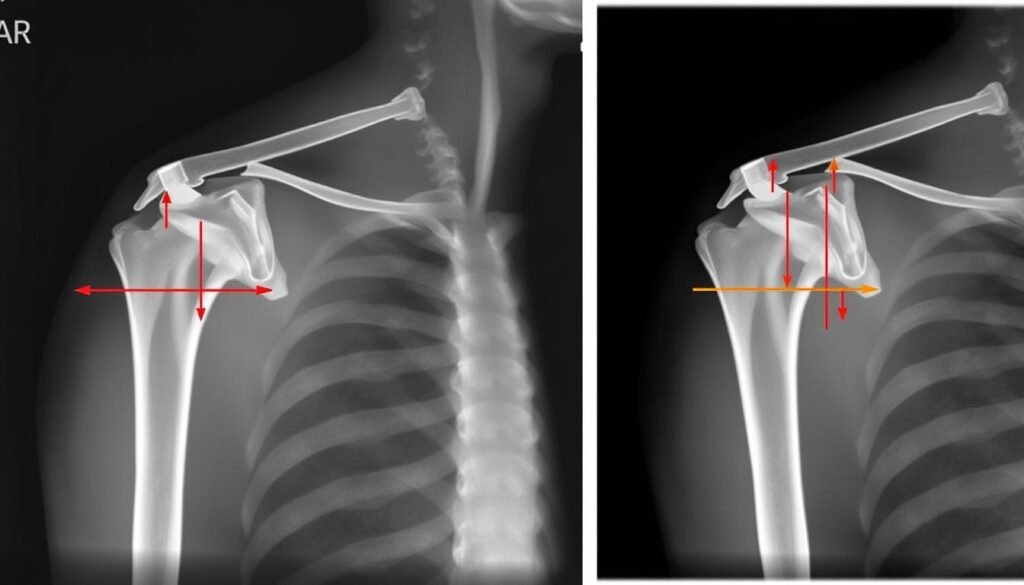

Röntgenbild einer AC Gelenk Verletzung mit Vergleich zur gesunden Seite

Röntgenaufnahme einer AC Gelenk Verletzung (Rockwood III) im Vergleich zur gesunden Seite

Röntgen

Standardaufnahmen der Schulter, oft mit Belastungsaufnahmen beider Schultern im Vergleich. Dabei wird ein Gewicht an den Armen befestigt, um den Grad der Instabilität zu beurteilen.